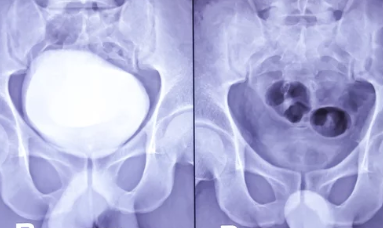

갑자기 소변이 마려워 참기 힘들거나, 화장실을 자주 가는 불편함을 겪고 계신가요? 혹시 과민성 방광은 아닐까요? 과민성 방광은 방광 근육이 과도하게 수축하여 빈뇨, 절박뇨, 야간뇨 등 다양한 배뇨 증상을 유발하는 질환입니다. 오늘은 과민성 방광 자가진단법을 통해 자신의 증상을 체크하고, 과민성 방광에 대한 정보와 치료 및 관리 방법까지 자세히 알려드립니다.

과민성 방광은 방광 근육의 과도한 수축으로 인해 발생하는 질환입니다.

정확한 원인은 밝혀지지 않았지만, 노화, 신경학적 질환, 비뇨기계 감염, 호르몬 변화, 약물 부작용, 카페인 과다 섭취 등 다양한 요인이 영향을 미치는 것으로 알려져 있습니다.